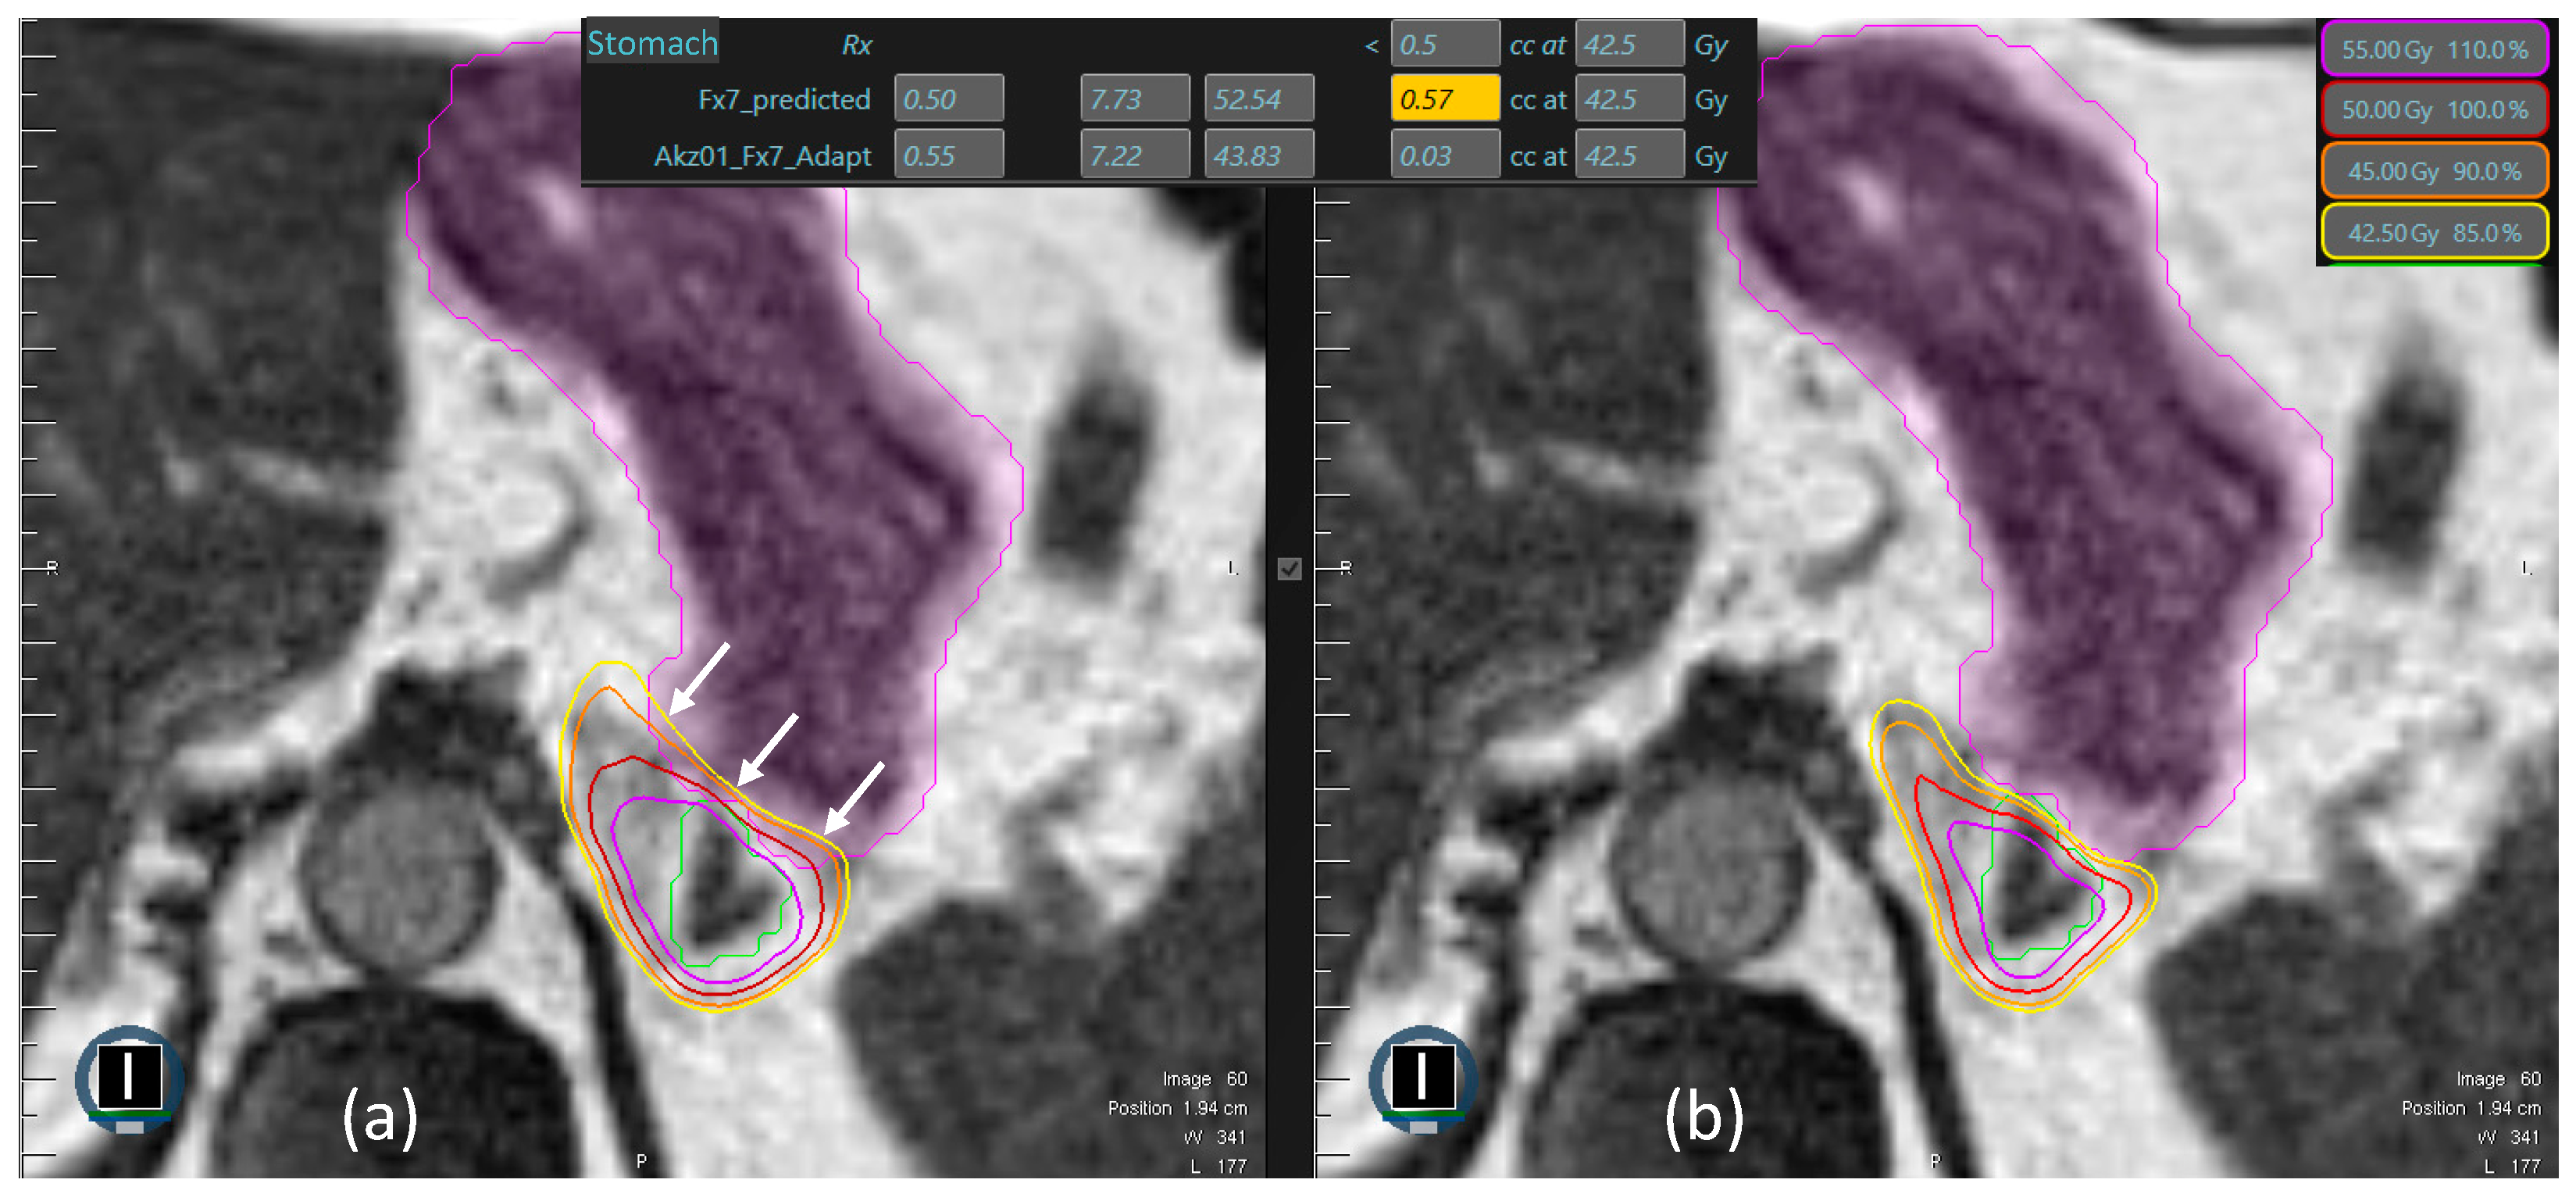

| Stomach | D0.5cc < 42.5 Gy |